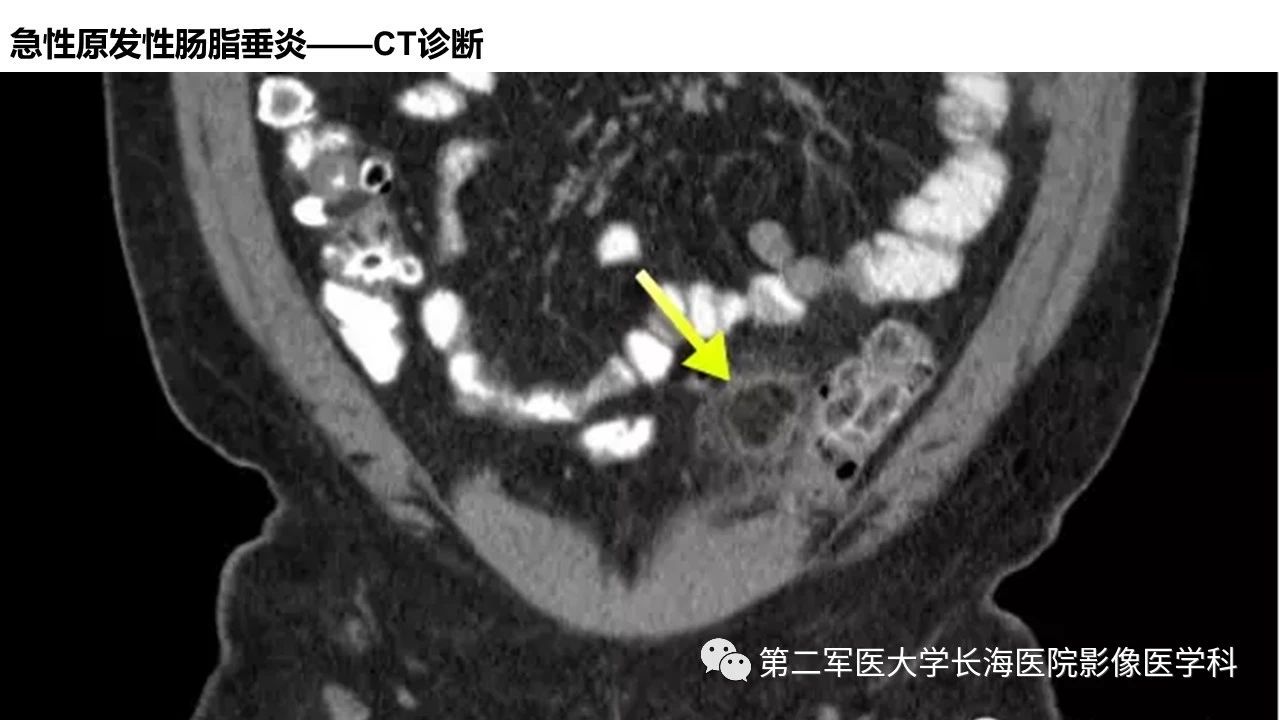

[腹盆] 急性原发性肠脂垂炎CT诊断与鉴别诊断

急性原发性肠脂垂炎CT诊断与鉴别诊断。

急性原发性肠脂垂炎CT诊断与鉴别诊断

来源:第二军医大学长海医院影像医学科